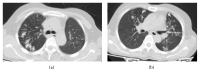

Giant cell tumour (GCT) is an uncommon primary bone tumour, and its multicentric presentation is exceedingly rare. We report a case of a 45-year-old female who presented to us with GCT of left distal radius. On the skeletal survey, osteolytic lesion was noted in her right sacral ala. Biopsy confirmed both lesions as GCT. Pulmonary metastasis was also present. Resection-reconstruction arthroplasty for distal radius and thorough curettage and bone grafting of the sacral lesion were done. Multicentric GCT involving distal radius and sacrum with primary sacral involvement is not reported so far to our knowledge.